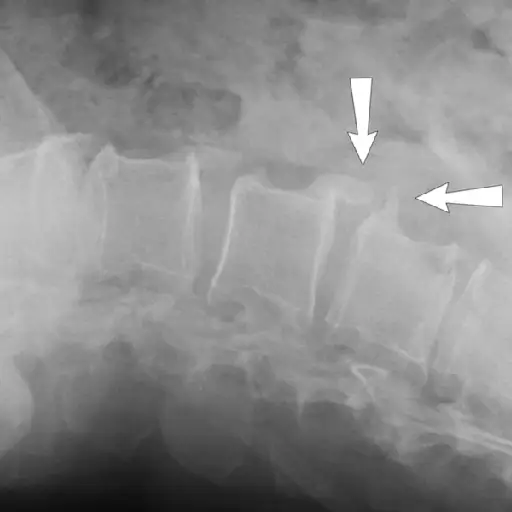

OA创造骨头

罗宾逊博士表示,骨头通过释放叫做成骨细胞的细胞对OA的损害反应,这是罗宾逊博士的形成。这可能最终导致骨突起 - 或骨赘。“这些结果在不再形成和正常轮廓的关节中,”罗宾逊博士说。它们可以沿着任何带有OA膝盖,臀部,脊柱,拇指的底座,或指关节(在顶部指关节的Kecodes的Knuckle的底部形成,以及中间指关节的Bouchard的节点)。大多数骨刺激不会引起疼痛,但它们可以改变关节的生物力学,导致更多的压力和加剧关节炎。

OA被诊断为X射线

oa和ra都要求您给出病史并进行临床检查进行诊断。但是对于诊断OA,X射线也很重要,说Ashany博士。X射线图像可以显示骨骼之间的空间是否变得越来越窄,软骨损失的标志。他们可以揭示那些称为骨折的骨骨生长。Askari博士说,磁共振成像(MRI)也可用于检测软骨和周围组织的更详细的变化。